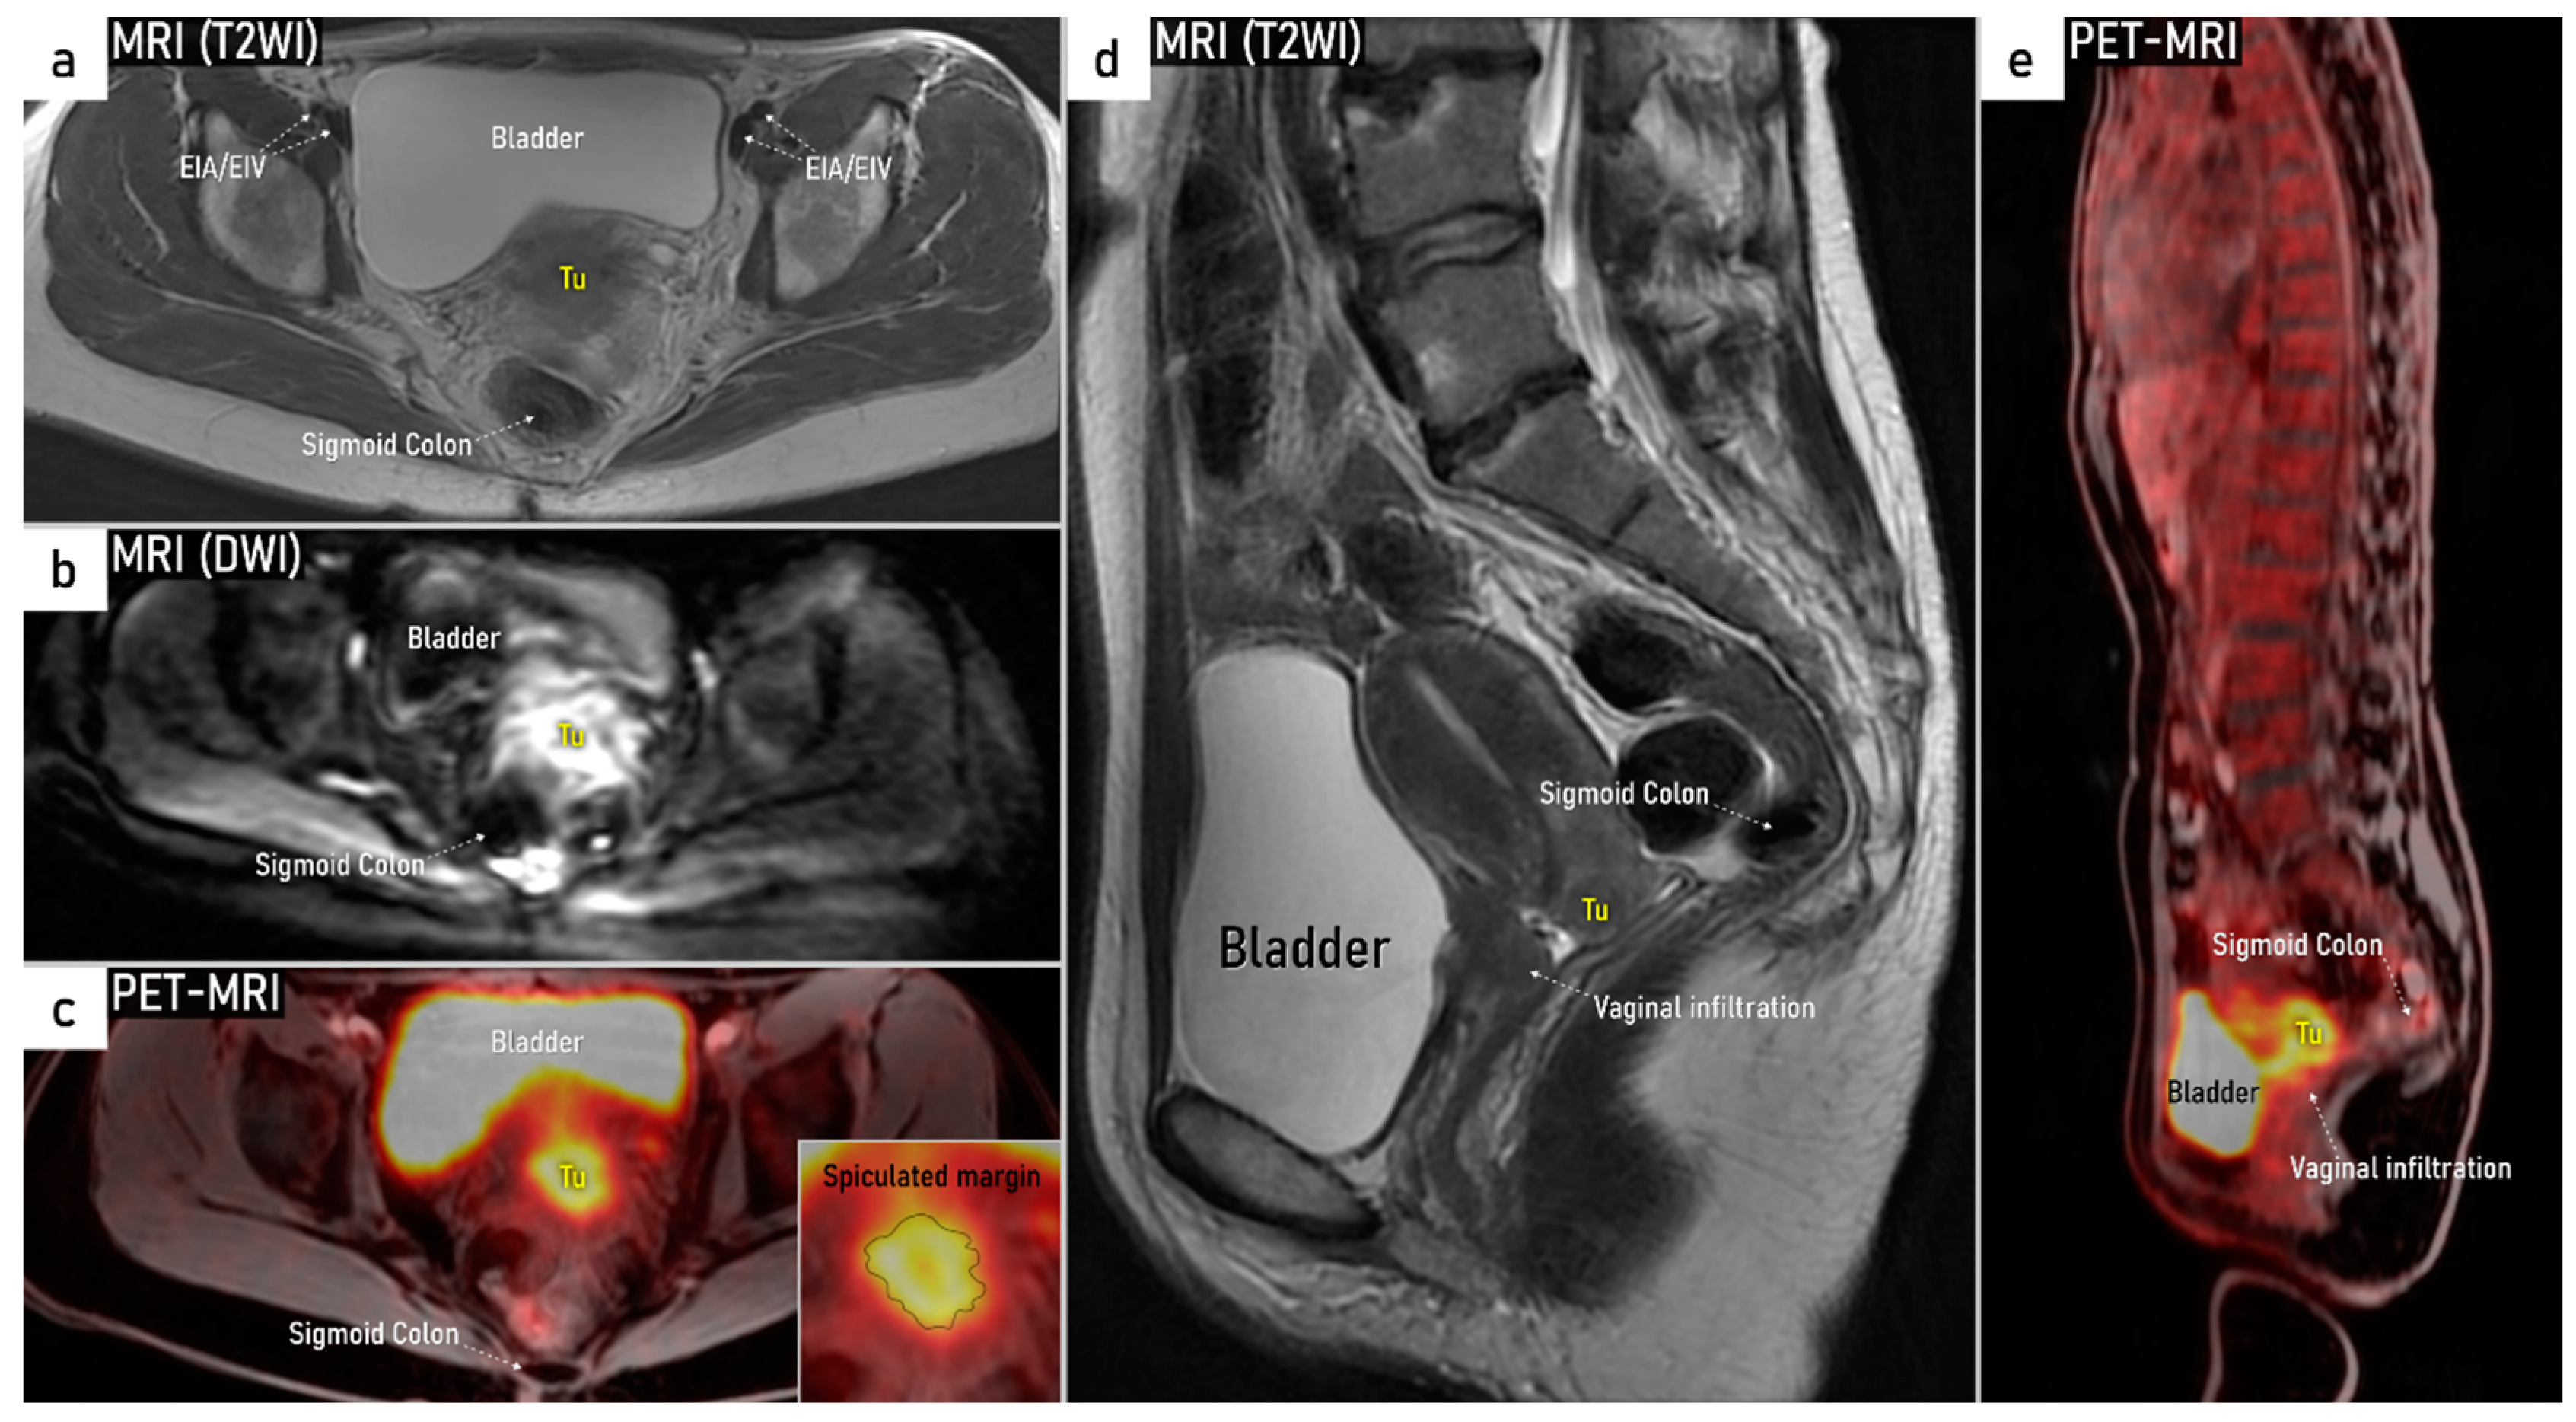

| T3e | IIIe | Carcinoma involves the lower third of the vagina and/or extends to the pelvic side wall and/or causes hydronephrosis or non-functioning kidney | Tumour infiltration of the lower third of vagina or lateral pelvic side wall. Pelvic side wall infiltration is considered when the tumour causes hydroureter, infiltrates the obturator internus, piriformis, and levator ani muscles, encases the iliac vessels, or invades the pelvic bones on US or MRI. |

| T3b | IIIB | Tumour extension to the pelvic side wall and/or hydronephrosis or non-functioning kidney (unless known to be due to other cause). | US: Hypoechogenic tumor projections up to pelvic side wall +/- infiltration of iliac vessels, ureters, muscles, presence of hydronephrosis MRI: Hyperintense infiltration up to the pelvic side wall, loss of normal parametrial signal intensity and increased signal intensity in pelvic musculature due to tumour invasion seen on T2W-images. |

3.3. Extrauterine extension (vagina, parametria, pelvic side wall, hydronephrosis and others)